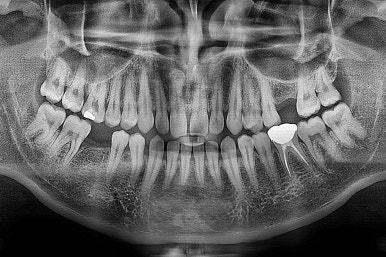

왼쪽이 치료 전, 오른쪽이 연산동임플란트 치료 후 X-ray 사진입니다.

전후 사진을 비교해 볼게요.